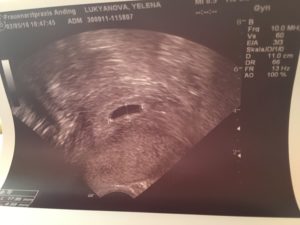

Нормальными показателями размеров зародыша принято считать:

- Внутренний диаметр плода равен 18–22 мм.

- Копчико-теменной размер зародыша достигает 3–6 мм. Данные актуальны на 28 день после подсаживания клетки.

- Желточный мешочек должен равняться 3 мм в диаметре.

Сведения не дают на 100% корректную картину, поскольку зависят от дня имплантации эмбриона. Обычно для наступления беременности необходимо 3–10 дней, в зависимости от подготовки среды в матке на день переноса зародышей. Сроки внедрения эмбрионов в матку еще зависят от дня продолжительности жизни бластоцисты. Обычно пятидневки быстрее имплантируют, чем трехдневки.